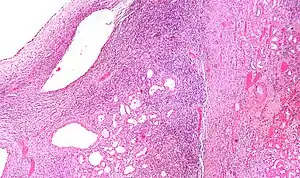

High magnification micrograph of a cystic nephroma showing the characteristic simple epithelium with hobnail morphology, and the ovarian-like stroma. H&E stain.

The characteristics of cystic nephromas are:

• Cysts lined by a simple epithelium with a hobnail morphology, i.e. the nuclei of the cyst lining epithelium bulges into the lumen of the cysts,

• Ovarian-like stroma that has a: